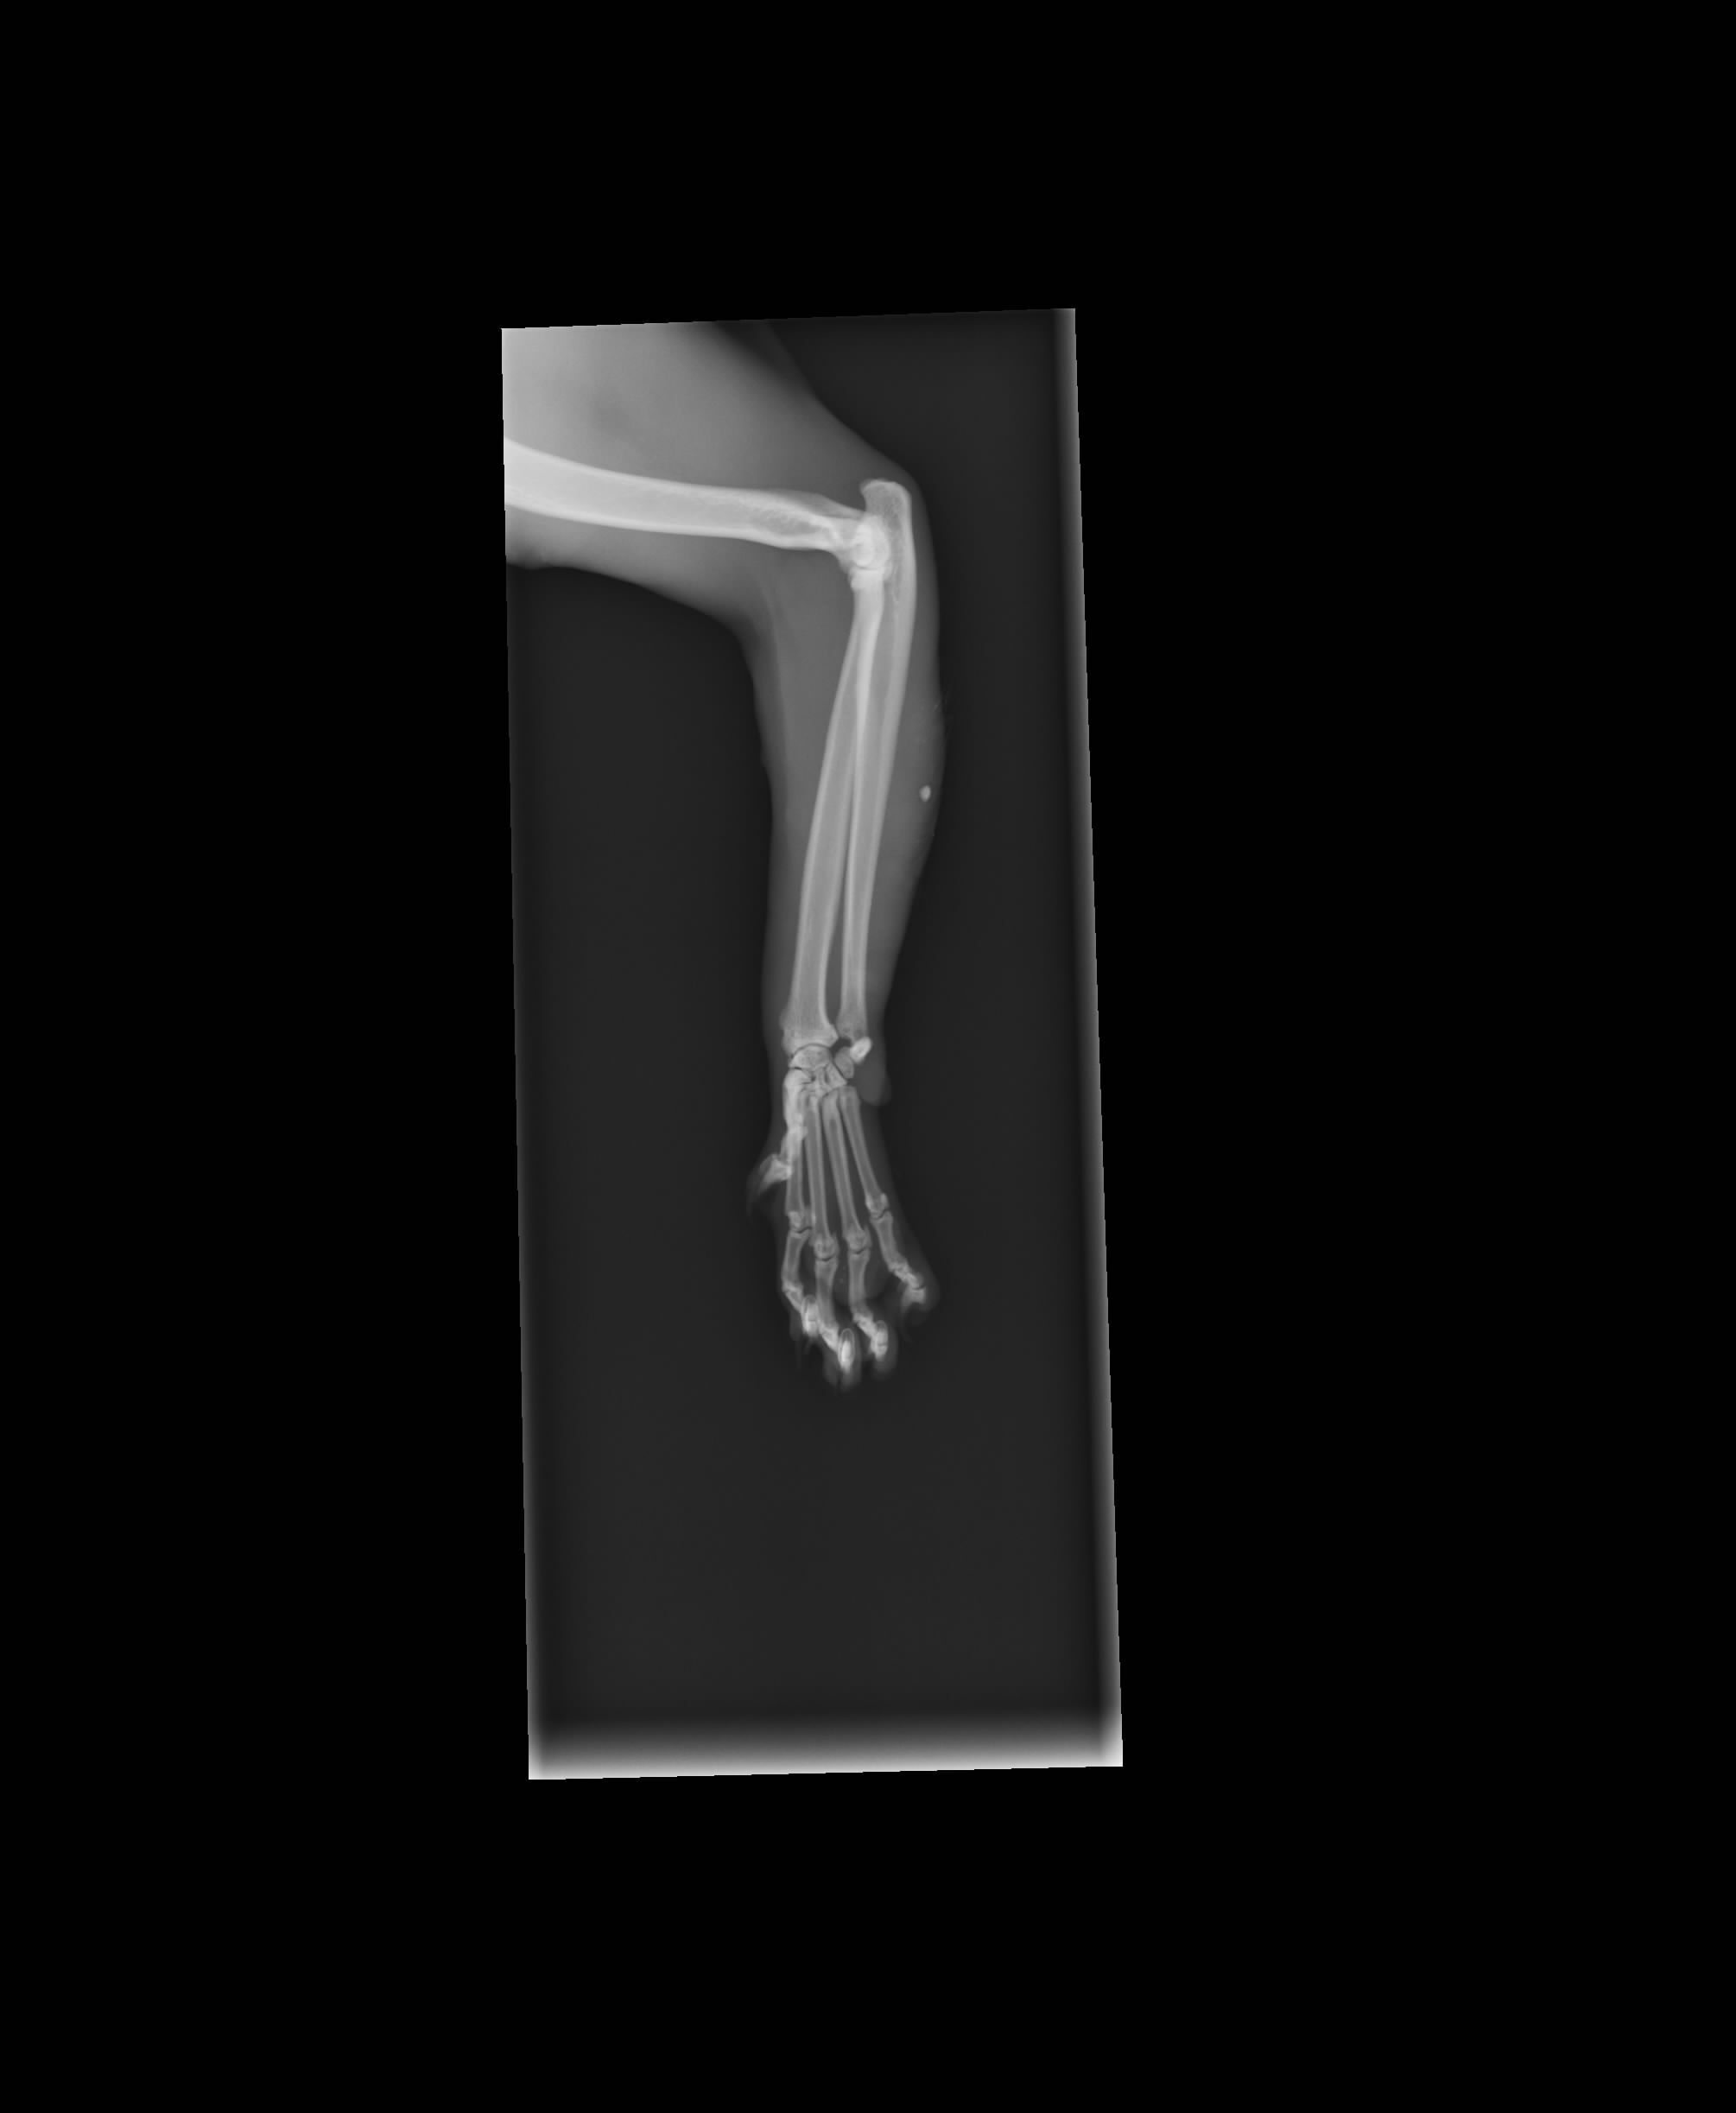

7/22晚上6:30左右送到與協會合作的杜犬貓專科動物醫院醫療,醫生評估過後需要住院12天,因為貓咪可能傷口有蜂窩性組織炎,也有可能有骨折,目前所要做的治療:照X光片 清理傷口 結紮 體內外驅蟲 血液檢查 除蚤 點滴抗生素治療!